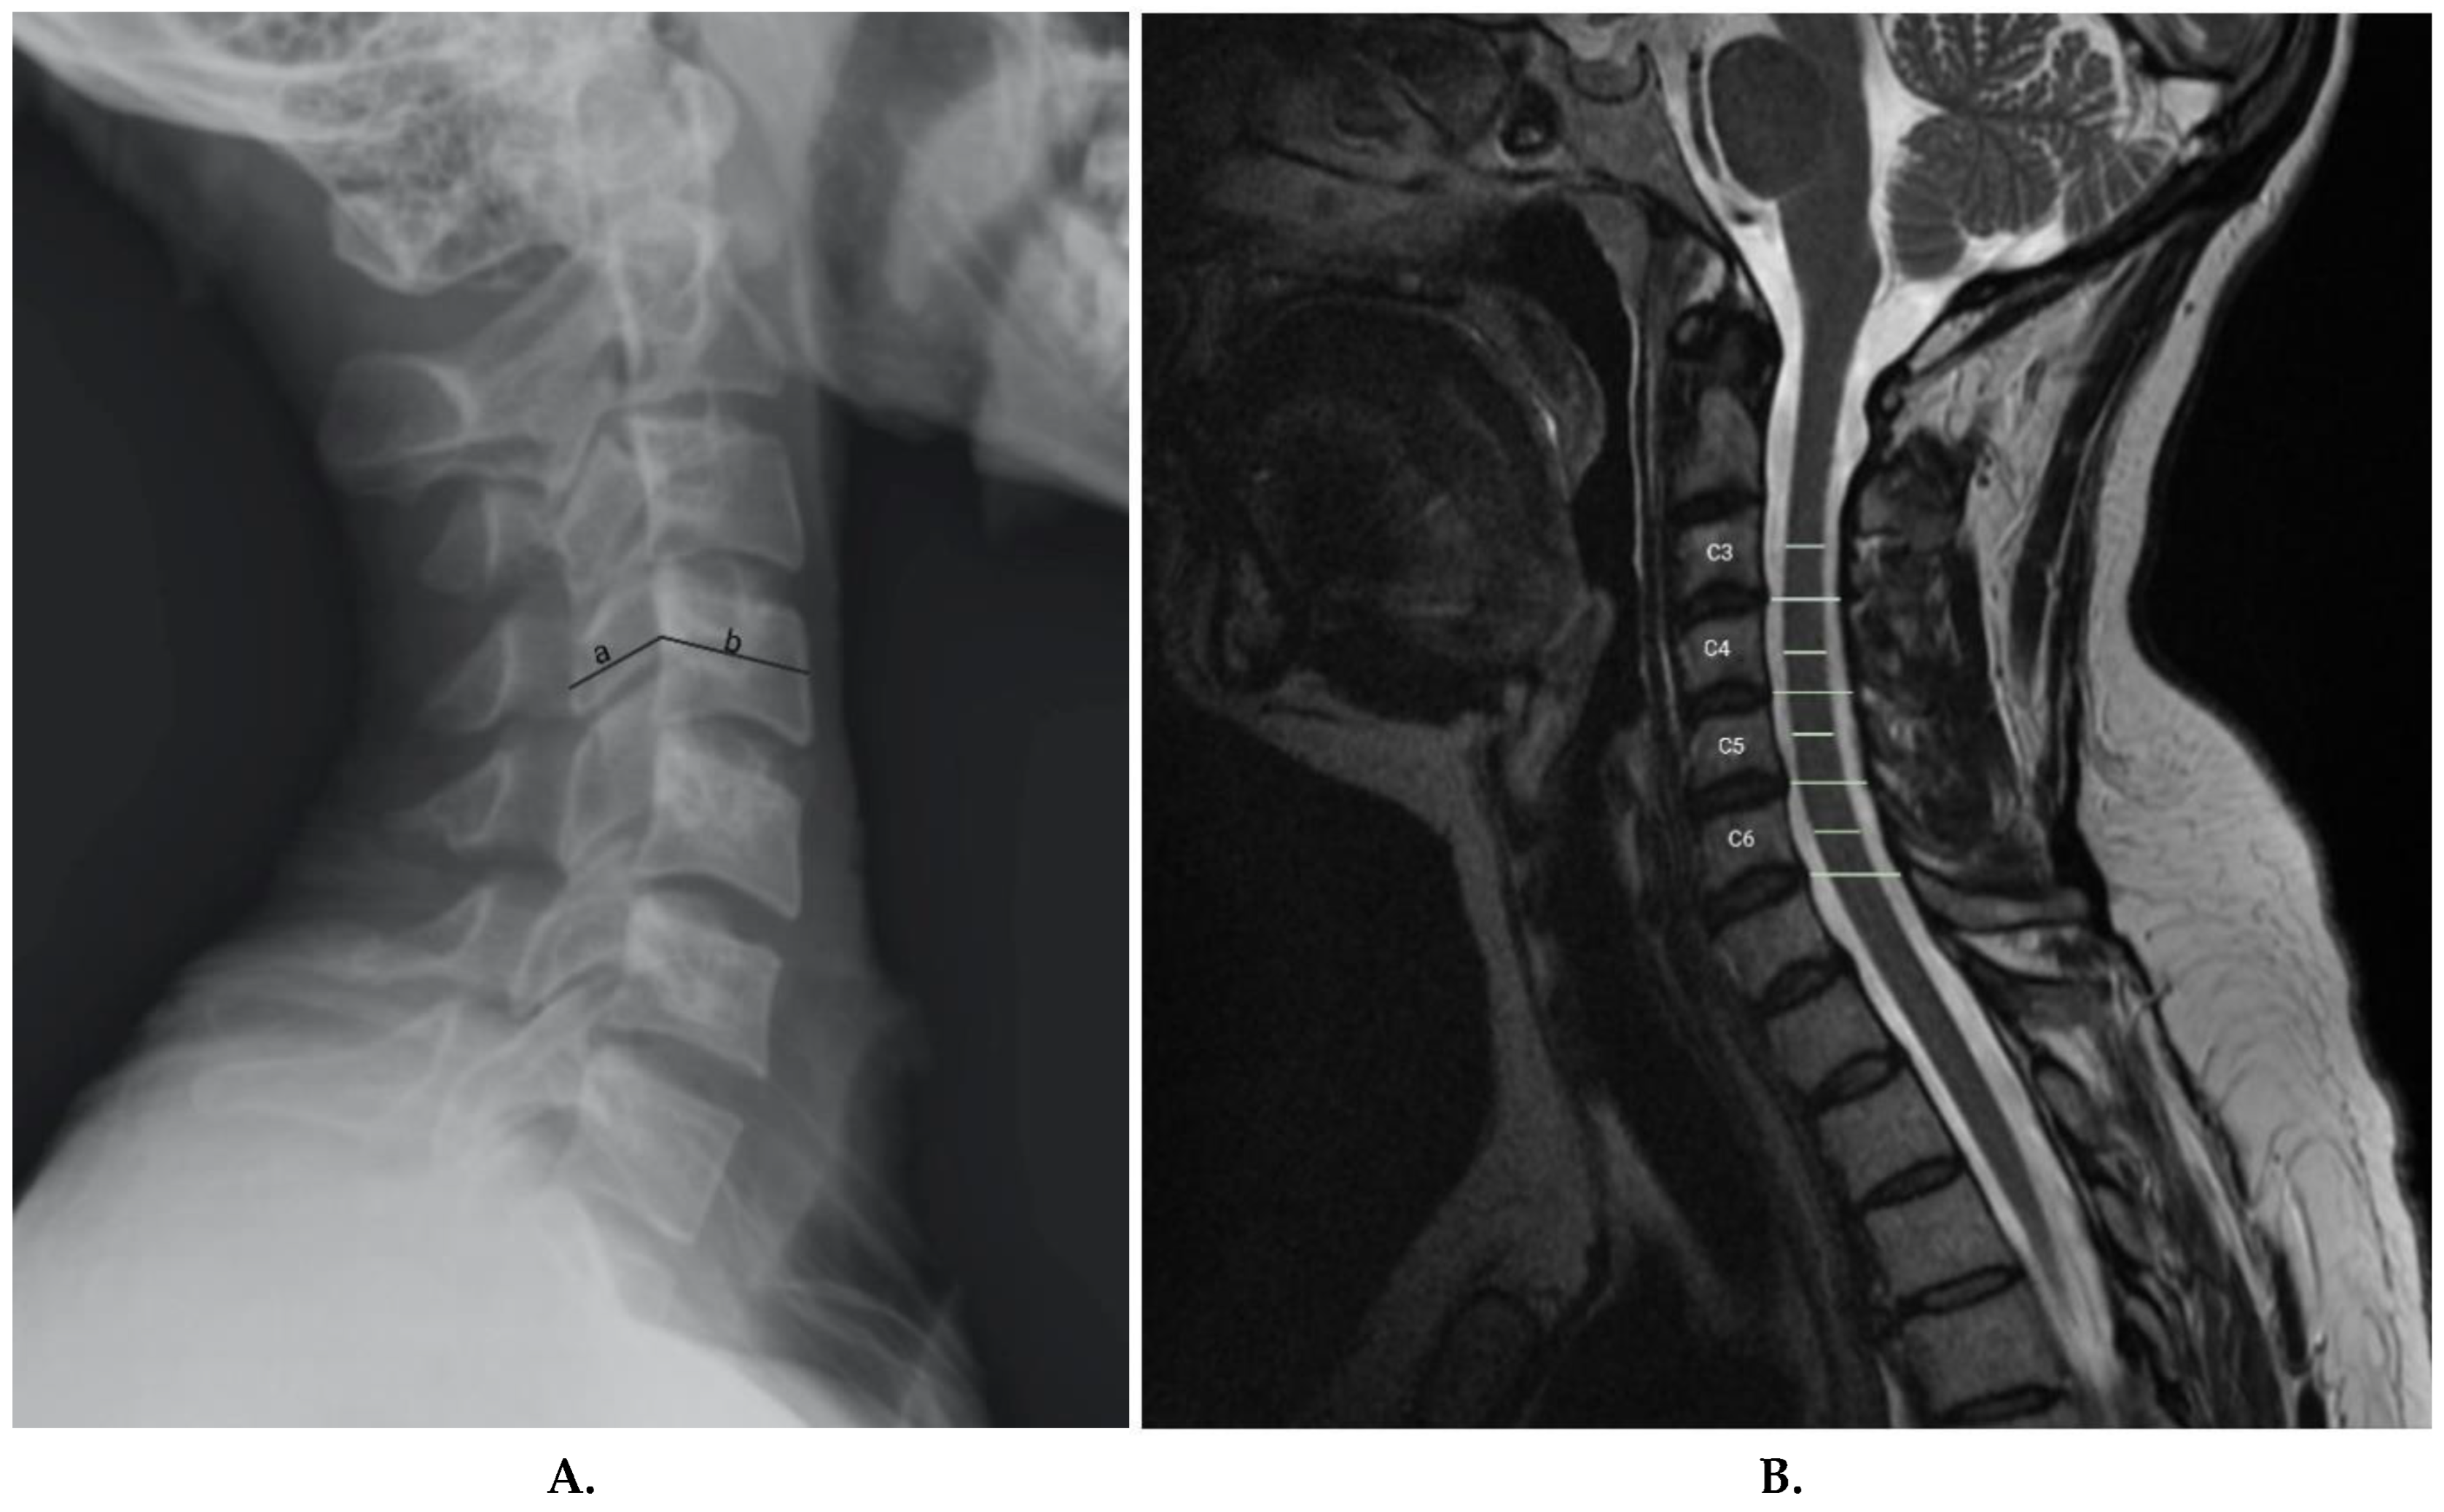

- Presciutti, S. M.; DeLuca, P.; Marchetto, P.; Wilsey, J. T.; Shaffrey, C.; Vaccaro, A. R. Mean subaxial space available for the cord index as a novel method of measuring cervical spine geometry to predict the chronic stinger syndrome in American football players. J Neurosurg Spine 2009, 11, 264–271. [Google Scholar] [CrossRef]

- Meyer, S. A.; Schulte, K. R.; Callaghan, J. J.; Albright, J. P.; Powell, J. W.; Crowley, E. T.; el-Khoury, G. Y. Cervical spinal stenosis and stingers in collegiate football players. Am J Sports Med 1994, 22, 158–166. [Google Scholar] [CrossRef]

- Kelly, J. D. t.; Aliquo, D.; Sitler, M. R.; Odgers, C.; Moyer, R. A. Association of burners with cervical canal and foraminal stenosis. Am J Sports Med 2000, 28, 214–217. [Google Scholar] [CrossRef]

- Greenberg, J.; Leung, D.; Kendall, J. Predicting chronic stinger syndrome using the mean subaxial space available for the cord index. Sports Health 2011, 3, 264–267. [Google Scholar] [CrossRef]

- Torg, J. S.; Naranja, R. J., Jr.; Pavlov, H.; Galinat, B. J.; Warren, R.; Stine, R. A. The relationship of developmental narrowing of the cervical spinal canal to reversible and irreversible injury of the cervical spinal cord in football players. J Bone Joint Surg Am 1996, 78, 1308–1314. [Google Scholar] [CrossRef]

- HERZOG, R. J.; WIENS, J. J.; DILLINGHAM, M. F.; SONTAG, M. J. Normal Cervical Spine Morphometry and Cervical Spinal Stenosis in Asymptomatic Professional Football Players: Plain Film Radiography, Multiplanar Computed Tomography, and Magnetic Resonance Imaging. Spine 1991, 16, S178–S186. [Google Scholar] [CrossRef]